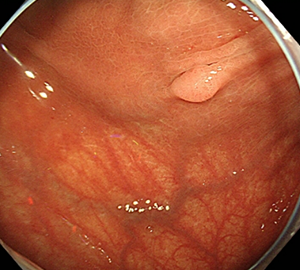

コールドスネアポリペクトミー(CSP)

合併症の非常に少ない優れた治療法であることから、近年大腸ポリープの外来切除法として急速に施行件数が増えてきています。当院ではこのコールドスネアポリペクトミーを主体としたポリープ切除を行っています。

| 1:ポリープを見つけます。 | 2:狭帯域光画像併用拡大観察で詳細に観察します。 | |

| 5:切除します。切除検体は吸引回収し病理検査を行います。 | 6:切除後に洗浄・観察して、病変の遺残ががないことを確認します。 |